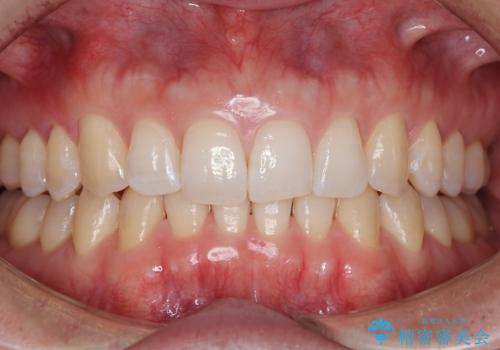

【非抜歯】インビザラインで正しい噛み合わせを

【非抜歯】インビザラインでガタつきと口元を改善!非抜歯でも印象が変わる矯正治療